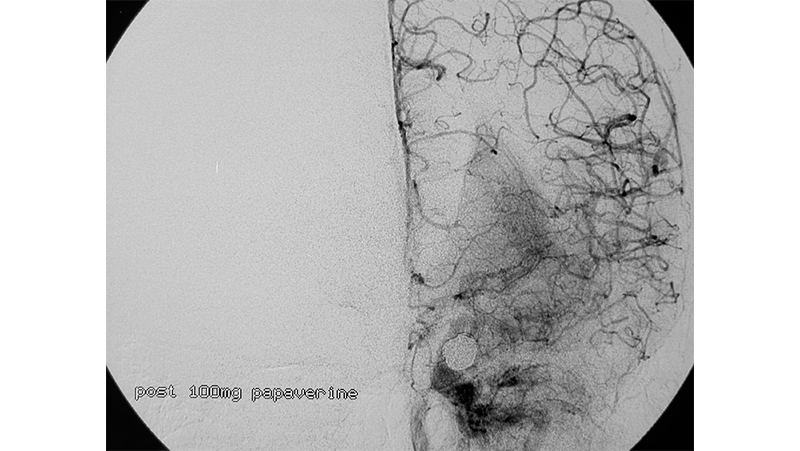

Εικόνα 4: Χορήγηση εκ νέου ενδαρτηριακά 100mg παπαβερίνης.